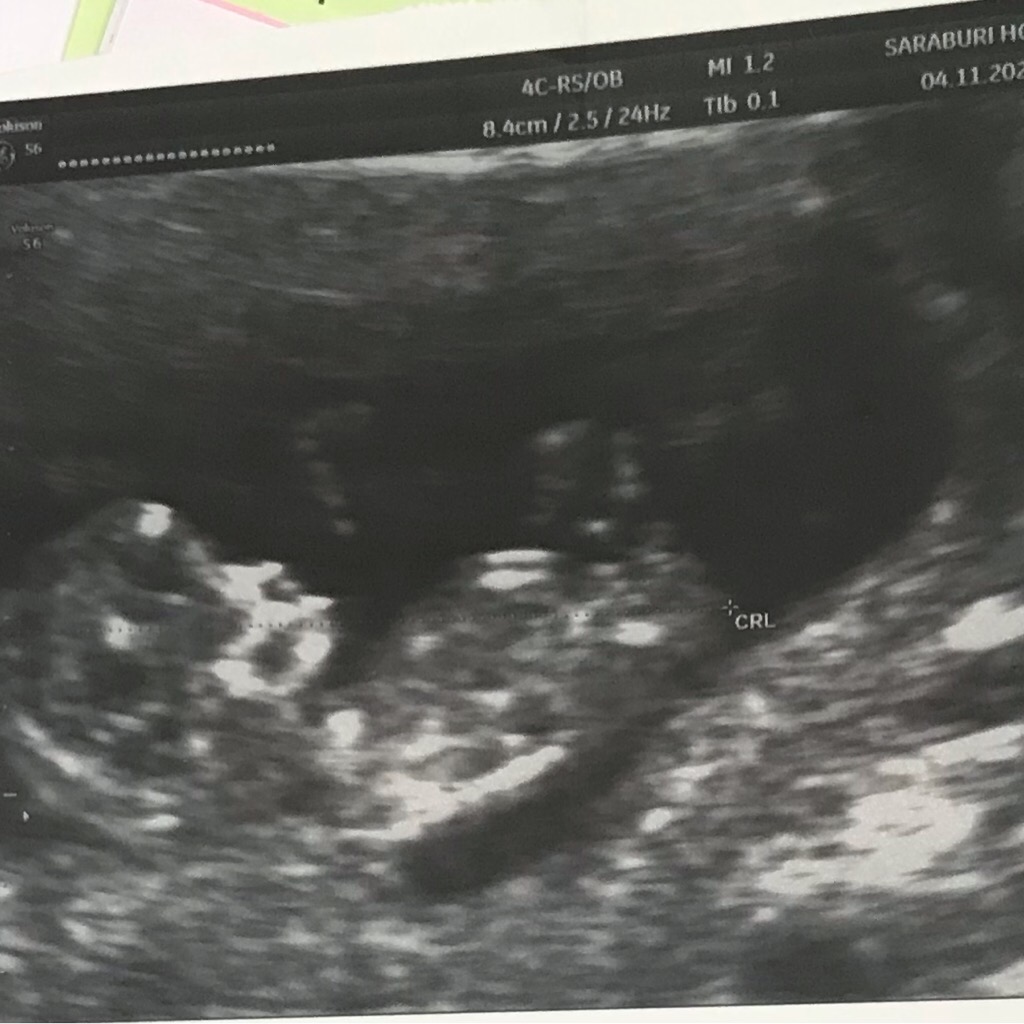

อัลตราซาวน์10+6Wค่ะ ช่วยดูหน่อยค่ะว่าในรูปเห็นอะไรบ้าง ดูไม่เป็นค่ะ